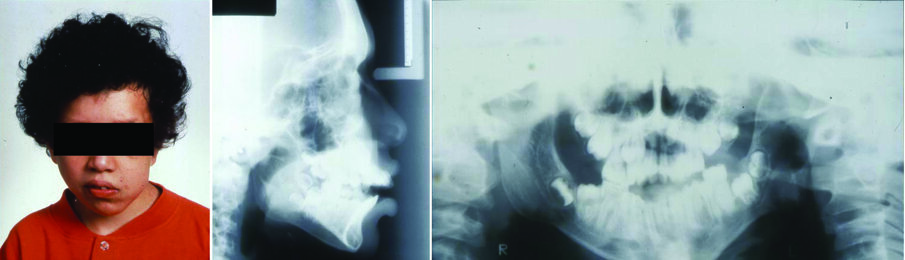

Genetics have been implicated in certain conditions such as multiple neurofibromatosis (Figure 1), hemifacial microsomia, cleft lip and palate.

Figure 1. Facial photograph of an 11-year-old girl with neurofibromatosis (a). The lesion is also apparent in lateral cephalometric (b) and panoramic (c) radiographs.